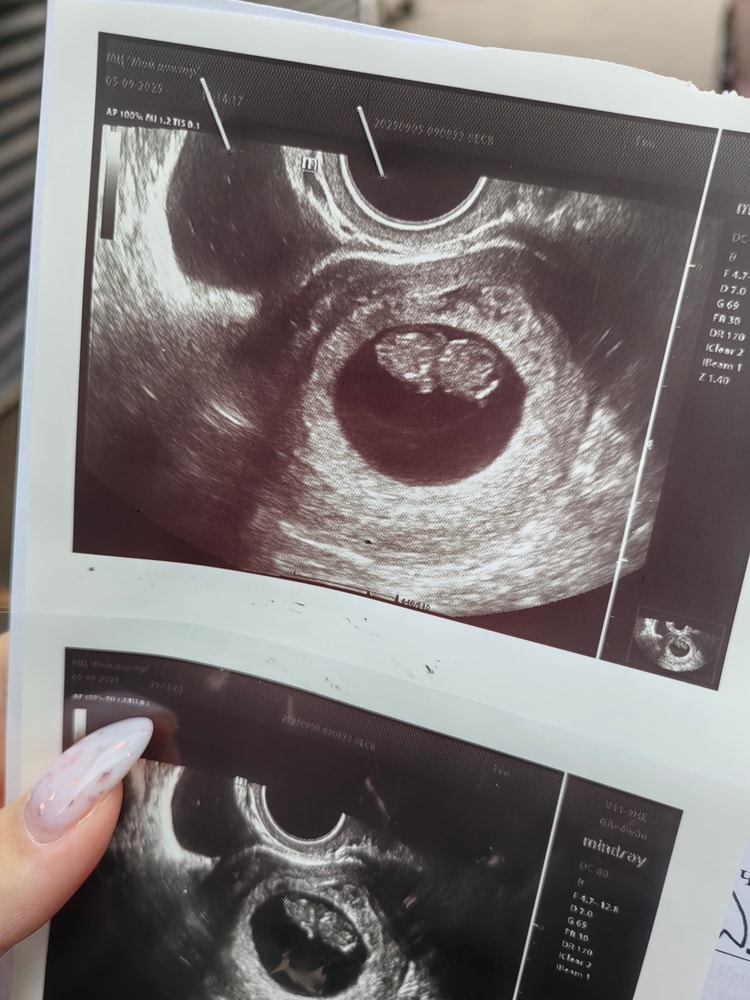

Обследования, узи, анализыНаше третье узи на сроке 9н3д.

Размерами прям как по приложению! (Наконец-то догнали, а то отставали на недельку) Ктр 23мм, чсс 156 у/м. Желточный мешочек 4мм